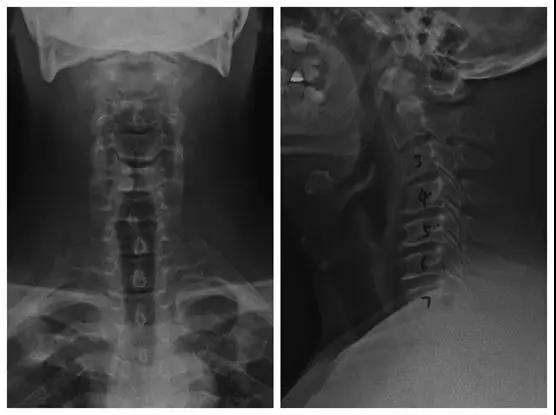

术前X线正、侧位片

术前核磁

术后X线正、侧位片